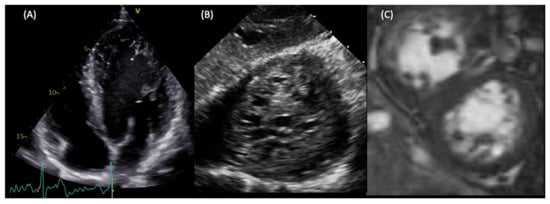

Figure 2.

LVNC in a young patient with no cardiological symptoms. The patients presented at the ER with paroxysmal atrial fibrillation. Transthoracic echocardiography showed hypertrabeculated LV (A). During a transoesophageal echocardiogram to rule out intra-atrial clots, the deep transgastric view at 0 degrees demonstrated the spongy aspect of the apex (B). CMR confirmed the diagnosis of LVNC using the Peterson criteria (C), and showed a mildly reduced ejection fraction.